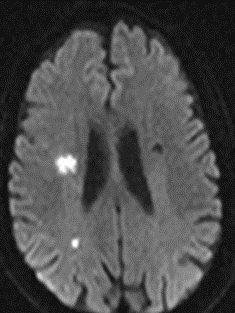

2022-07-21 颅脑MR。

DWI

MRA

重要影像结论:左侧额顶枕叶梗死灶。